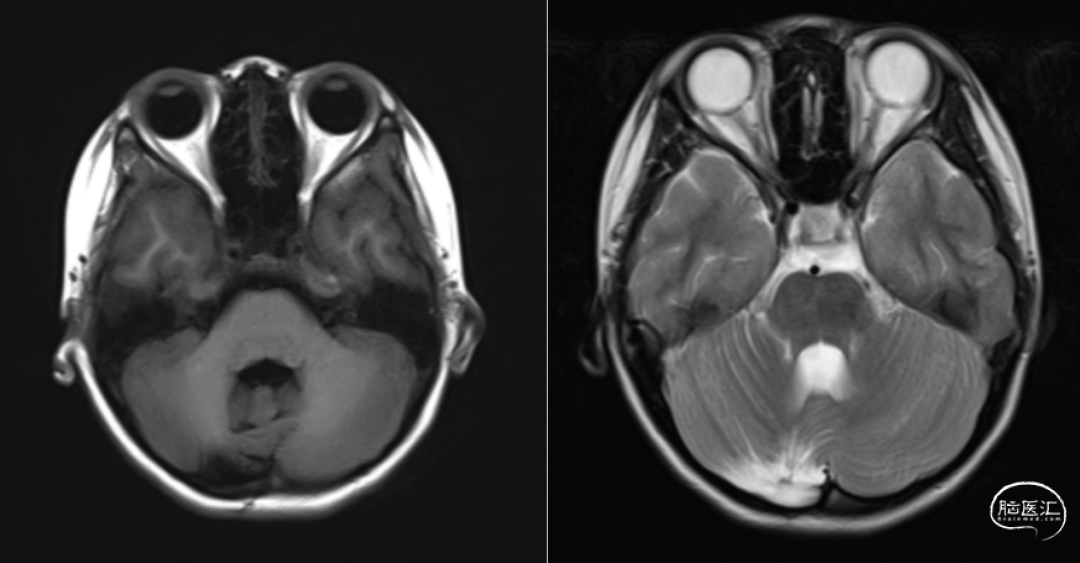

入院后进一步完善相关检查检验。头部增强磁共振提示:右侧小脑半球占位,考虑星形细胞瘤可能性大(图1)。完善各项术前准备后行右侧小脑半球肿瘤切除术,经过顺利,术中见肿瘤位于右侧小脑半球,肿瘤灰白色,呈实性,质地偏软,血供丰富,有完整包膜,和正常小脑组织粘连紧密,切除部分肿瘤送冰冻病理提示“毛细胞星形细胞瘤”,于肿瘤包膜外剥离肿瘤和小脑粘连,肿瘤全切。术后复查CT及MR显示肿瘤全切(图2)。手术后无神经功能影响,未行放疗化疗,每年复查头部增强磁共振,常规随访。

影像学表现上,毛细胞型星形细胞瘤的T2加权像通常表现为高信号,T1信号多变[2]。在颅后窝和大脑半球,大多数毛细胞型星形细胞瘤表现为界限清楚、扩张的肿块,包括强化的壁结节,周围有囊肿。根据囊变程度,可分为三型:1.囊肿型:病变呈囊性,没有壁结节或实性肿块;2.囊肿结节型:以囊性病变为主,伴有壁结节;3.肿块性:病变以实性部分为主,伴有或不伴有囊变。本例患者MR表现以实性部分为主,强化明显。